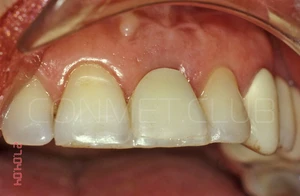

Ситуация в полости рта через 10 лет после операции. Обратите внимание на сохранность межзубных сосочков около имплантата и полное отсутствие рецессии десны на поддесневой, полированной части имплантата.

Фото этой же коронки через 15 лет после операции.